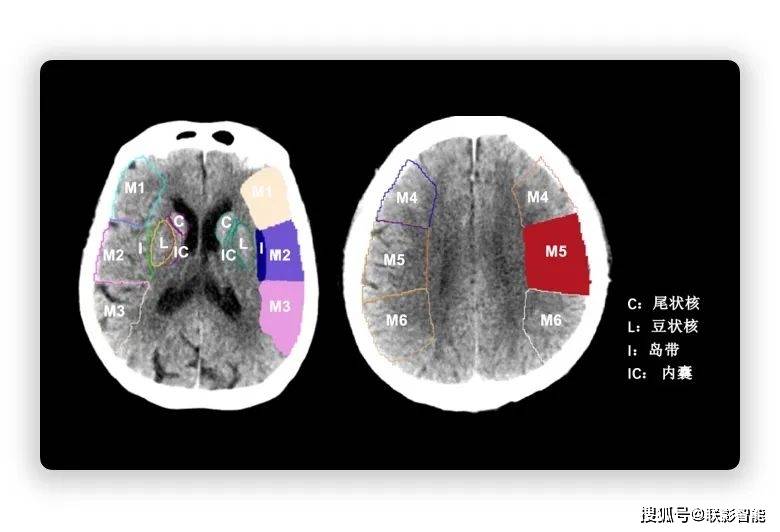

aspect评分脑分区彩图

aspect评分选择两个ct层面,给不同供血区域赋予分值,每个区域为1分,如

ct 评分(alberta stroke program early ct score,aspects)是评价缺血